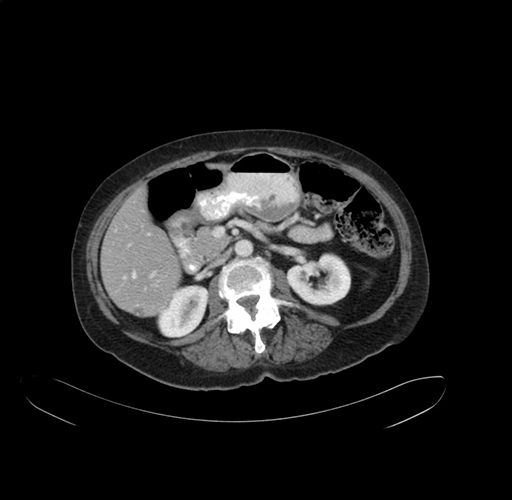

Pre-Chemo: Axial Venous

Axial Venous